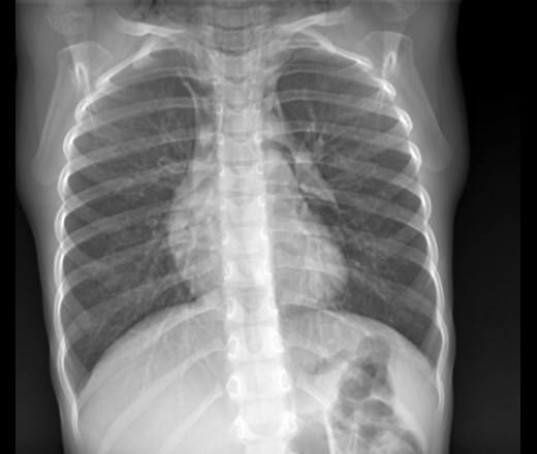

Пневмомедиастинум при проникающих ранениях трахеи или главных бронхов представляет собой крайне опасное состояние, характеризующееся попаданием воздуха в средостение. Согласно данным медицинских отчетов из зоны СВО, такая патология встречается в 4-6% случаев торакальных ранений и отличается стремительным развитием — от момента травмы до критического состояния проходит не более 15-30 минут. Особенностью является быстрое нарастание давления в средостении, что приводит к сдавлению сердца и магистральных сосудов.

Клиническая картина проявляется триадой характерных симптомов: внезапная боль за грудиной, усиливающаяся при глотании и глубоком вдохе; подкожная эмфизема, распространяющаяся на шею и лицо; нарастающая одышка с признаками дыхательной недостаточности. При аускультации часто выявляется симптом Хаммана — крепитация синхронно с сердечными сокращениями. В полевых условиях диагностика основывается на выявлении этих признаков, так как рентгенологическое исследование обычно недоступно.